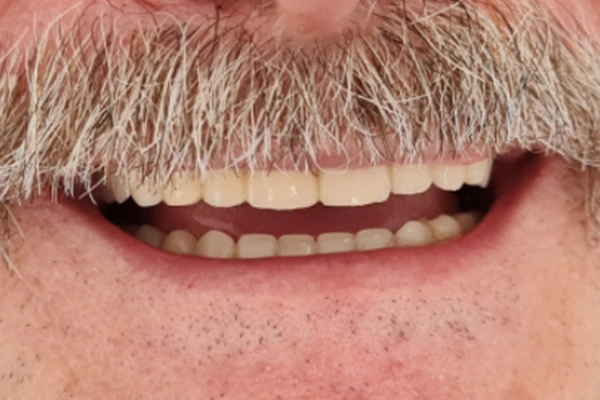

PRIJE I POSLijE

I can’t change the world, but I can change your smile!